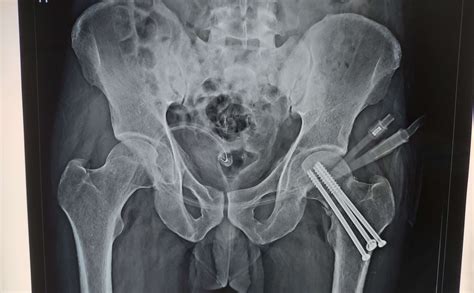

Internal fixation is often used for fractures where the bone pieces can be realigned. During this procedure, the surgeon uses metal screws, plates, or rods to hold the bones together while they heal naturally. This option is frequently chosen when the blood supply to the head of the femur remains intact, as it preserves the patient's own joint.

Internal Fixation Stable fractures with good bone quality Uses screws, plates, or pins; preserves the patient's natural bone